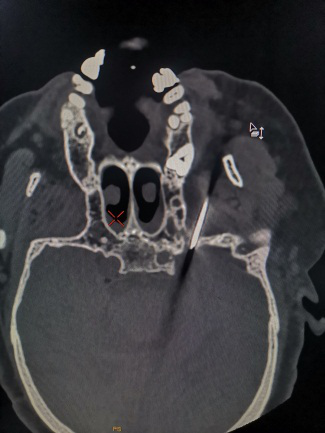

2022年1月18日,我院疼痛科在CT室、手术室的配合下,完成第一例CT引导下经皮穿刺三叉神经根部分毁损手术,手术过程顺利,效果理想,患者满意。

在对患者病情充分评估情况下,结合影像学资料及病人体征,门诊拟“三叉神经痛”收住入院,完善入院常规检查,科主任柴林涛对患者的基础条件及病情的分析后,组织科室讨论,最终拟定行局麻CT引导下经皮穿刺三叉神经感觉根部分切断术,完善术前准备工作,于1月18日在CT手术室行手术治疗。

术前结合CT平扫影像检查资料,制定了安全的穿刺路线,手术进展顺利,术中患者血压一度达到收缩压195MMHG、舒张压110MMHG,患者肯定存在心理因素,为此手术室护士长柴从云握着患者的手,对其进行心理疏导,缓解其紧张情绪,让病人安心的接受了手术。术中穿刺调针历时15分钟左右,射频毁损用时3分钟,接行术过程紧凑,环节对接顺畅,术毕,患者疼痛立刻缓解。(何厚鹏)